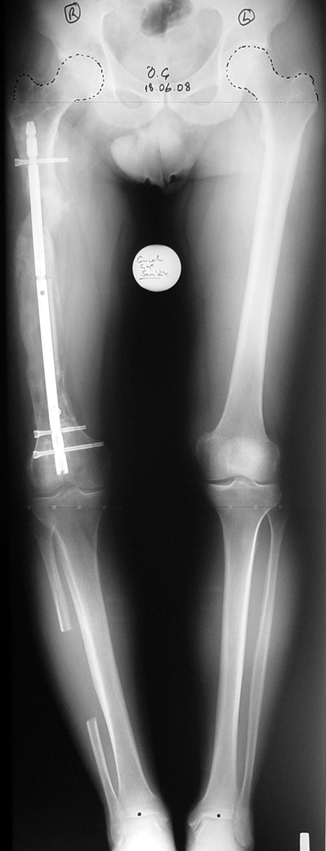

Kas ve iskelet sistemi enfeksiyonları, sık karşılaşılan bir sorundur. Yeni evreleme sistemleri, gelişmiş cerrahi teknikler, ve hiperbarik oksijen tedavisi gibi destek tedavileri sayesinde kronik osteomiyelit tedavisi son 20 yıl içinde büyük ölçüde değişmiştir.

Kronik osteomiyelit, kemik ve yumuşak dokularda nekroza yol açar. Ölü kemik, patojen mikroorganizmalara ev sahipliği yapan bir nidus oluşturur. Konağın savunma sistemleri, mikroorganizmalarla baş etmek için sıklıkla optimal koşullarda değildir. Dolaşım bozukluğu yüzünden enfeksiyon bölgesine antibiyotikler yeterince ulaşamaz. Bu nedenle ölü dokuların ortamdan tamamen uzaklaştırılması gerekir (radikal debridman).

Uygun radikal debridman tüm nekrotik kemik ve yumuşak dokuların çıkartılmasını gerektirir, ve sıklıkla uzuvda instabiliteye neden olur. Kalan kemik ve yumuşak doku defektinin bir şekilde fiksasyonu ve rekonstrüksiyonu gereklidir. İlizarov’un ortaya koyduğu distraksiyon osteogenezi yöntemi, kaynamanın elde edilmesi, deformitenin düzeltilmesi, bacak boy eşitsizliğinin giderilmesi ve segmental defektlerin rekonstrükte edilmesi için başarıyla kullanılmaktadır.

Eksternal fiksatör ile geçen süre (eksternal fiksasyon indeksi), gereken distraksiyon miktarına bağlıdır ve bu süre boyunca bazı komplikasyonlarla karşılaşılabilir. Distraksiyon dönemi sona erdikten sonra, distraksiyon süresinin iki katını aşan konsolidasyon döneminde hastalar eksternal fiksatörü zorlukla tolere edebilirler. Yeterli konsolidasyon sağlanmadan eksternal fiksatör çıkartılırsa ise kırıklar, deformite ve kısalık oluşabilir. Hastanın fiksatör ile birlikte geçirdiği sürenin azaltılması ve böylece hasta konforunun ve aktivite düzeyinin arttırılması için intramedüller çivi üzerinden uzatma yöntemi uygulanmaktadır. Bu yöntemde distraksiyon dönemi sona erdiğinde kemiğin içindeki çivi statik olarak kilitlenmekte ve eksternal fiksatör çıkartılmaktadır. Stabilizasyon intramedüller çivi tarafından sağlandıktan sonra konsolidasyon dönemi gerçekleşmektedir. Bu şekilde hem eksternal fiksatörün uzun süre kalmasından hem de erken çıkartılmasından kaynaklanan komplikasyonların önüne geçilmektedir.